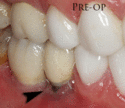

Recession of the gingiva leads to exposure of the metal abutment under a dental crown.

Dental cement under the gingiva causes peri-implantitis and implant failure.